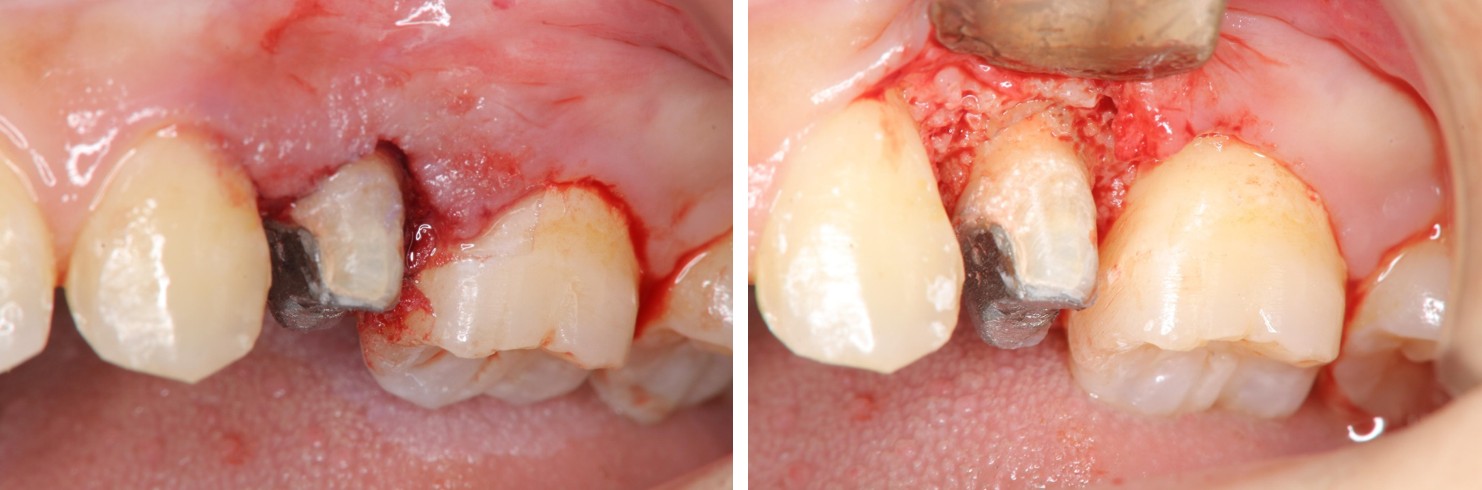

水雷射牙冠增長手術